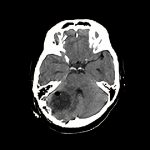

転移性脳腫瘍

断層撮影

手術前1

手術後

No.’12_125 手術前1

No.’12_125 手術後